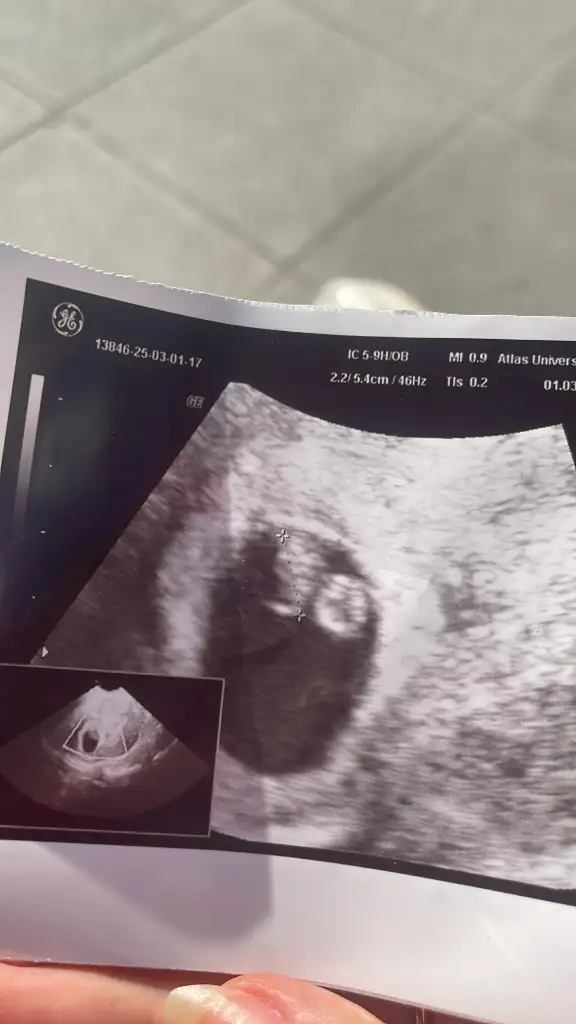

Merhaba onun nub teorisine göre çıkıntısı paralel durduğu için kız diye tahmin ettim,sizin görüntü karından alındıysa ramzi teorisine göre erkek duruyor6 haftalik tahminde bulu

Sizin görüntüyü göremedim atar mısın bi dahaBende çok merak ediyorum sağlıklı olsun tabi bana da tahmin yapabilirmisiniz